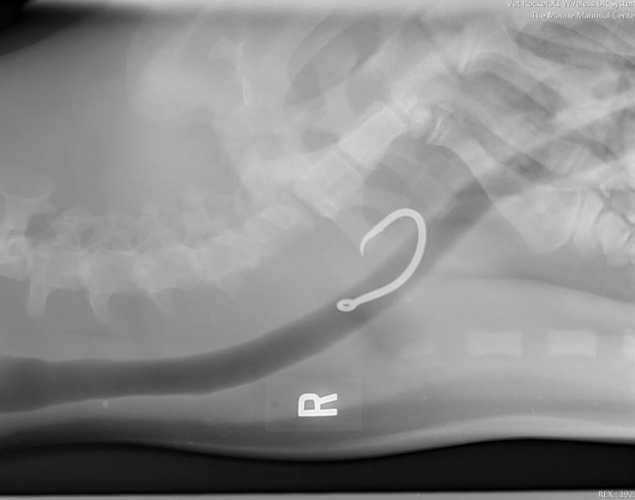

An X-ray of the animal’s throat and chest, taken with a portable Vet Rocket X-ray machine, had confirmed that the seal had ingested a large fishing hook, which had become embedded in the lining of his esophagus.

After several hours of delicate maneuvering, the two-inch hook was successfully removed. But the surgery—and the danger to the monk seal—wasn’t over yet.